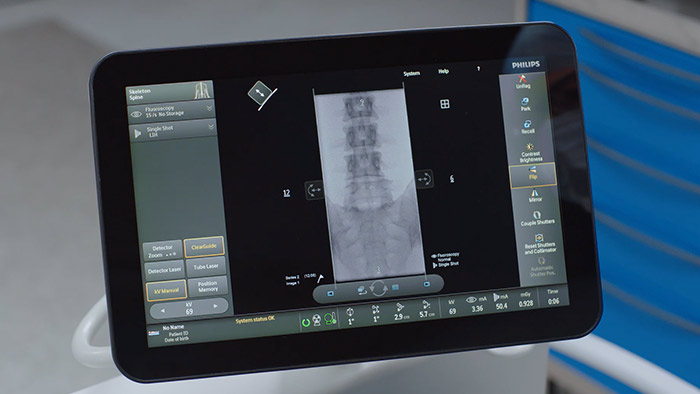

Touch screen module The Touch screen module5 (TSM) is designed to deliver value by enhancing the clinical capabilities of Zenition 70. As an addition to the Zenition 70 platform, the TSM supports full table-side control for surgeons during procedures.